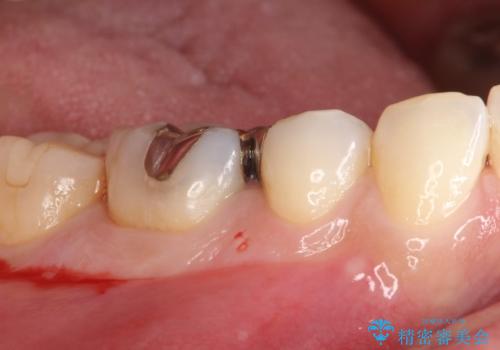

- メタルインレーによる審美障害を主訴に来院されました。

セラミックインレーに治療を行っております。

e-max プレスインレーにて修復治療を行っているため適合性及び審美性の高い治療を行うことができます。